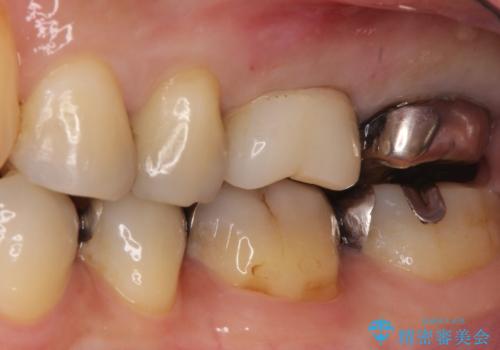

【再根管治療】オールセラミッククラウンによる修復

- 治療途中の歯があることを主訴に来院されました。

根管治療を行なったのちオールセラミックにて修復治療を行なっております。

第二大臼歯の治療は希望されませんでした。